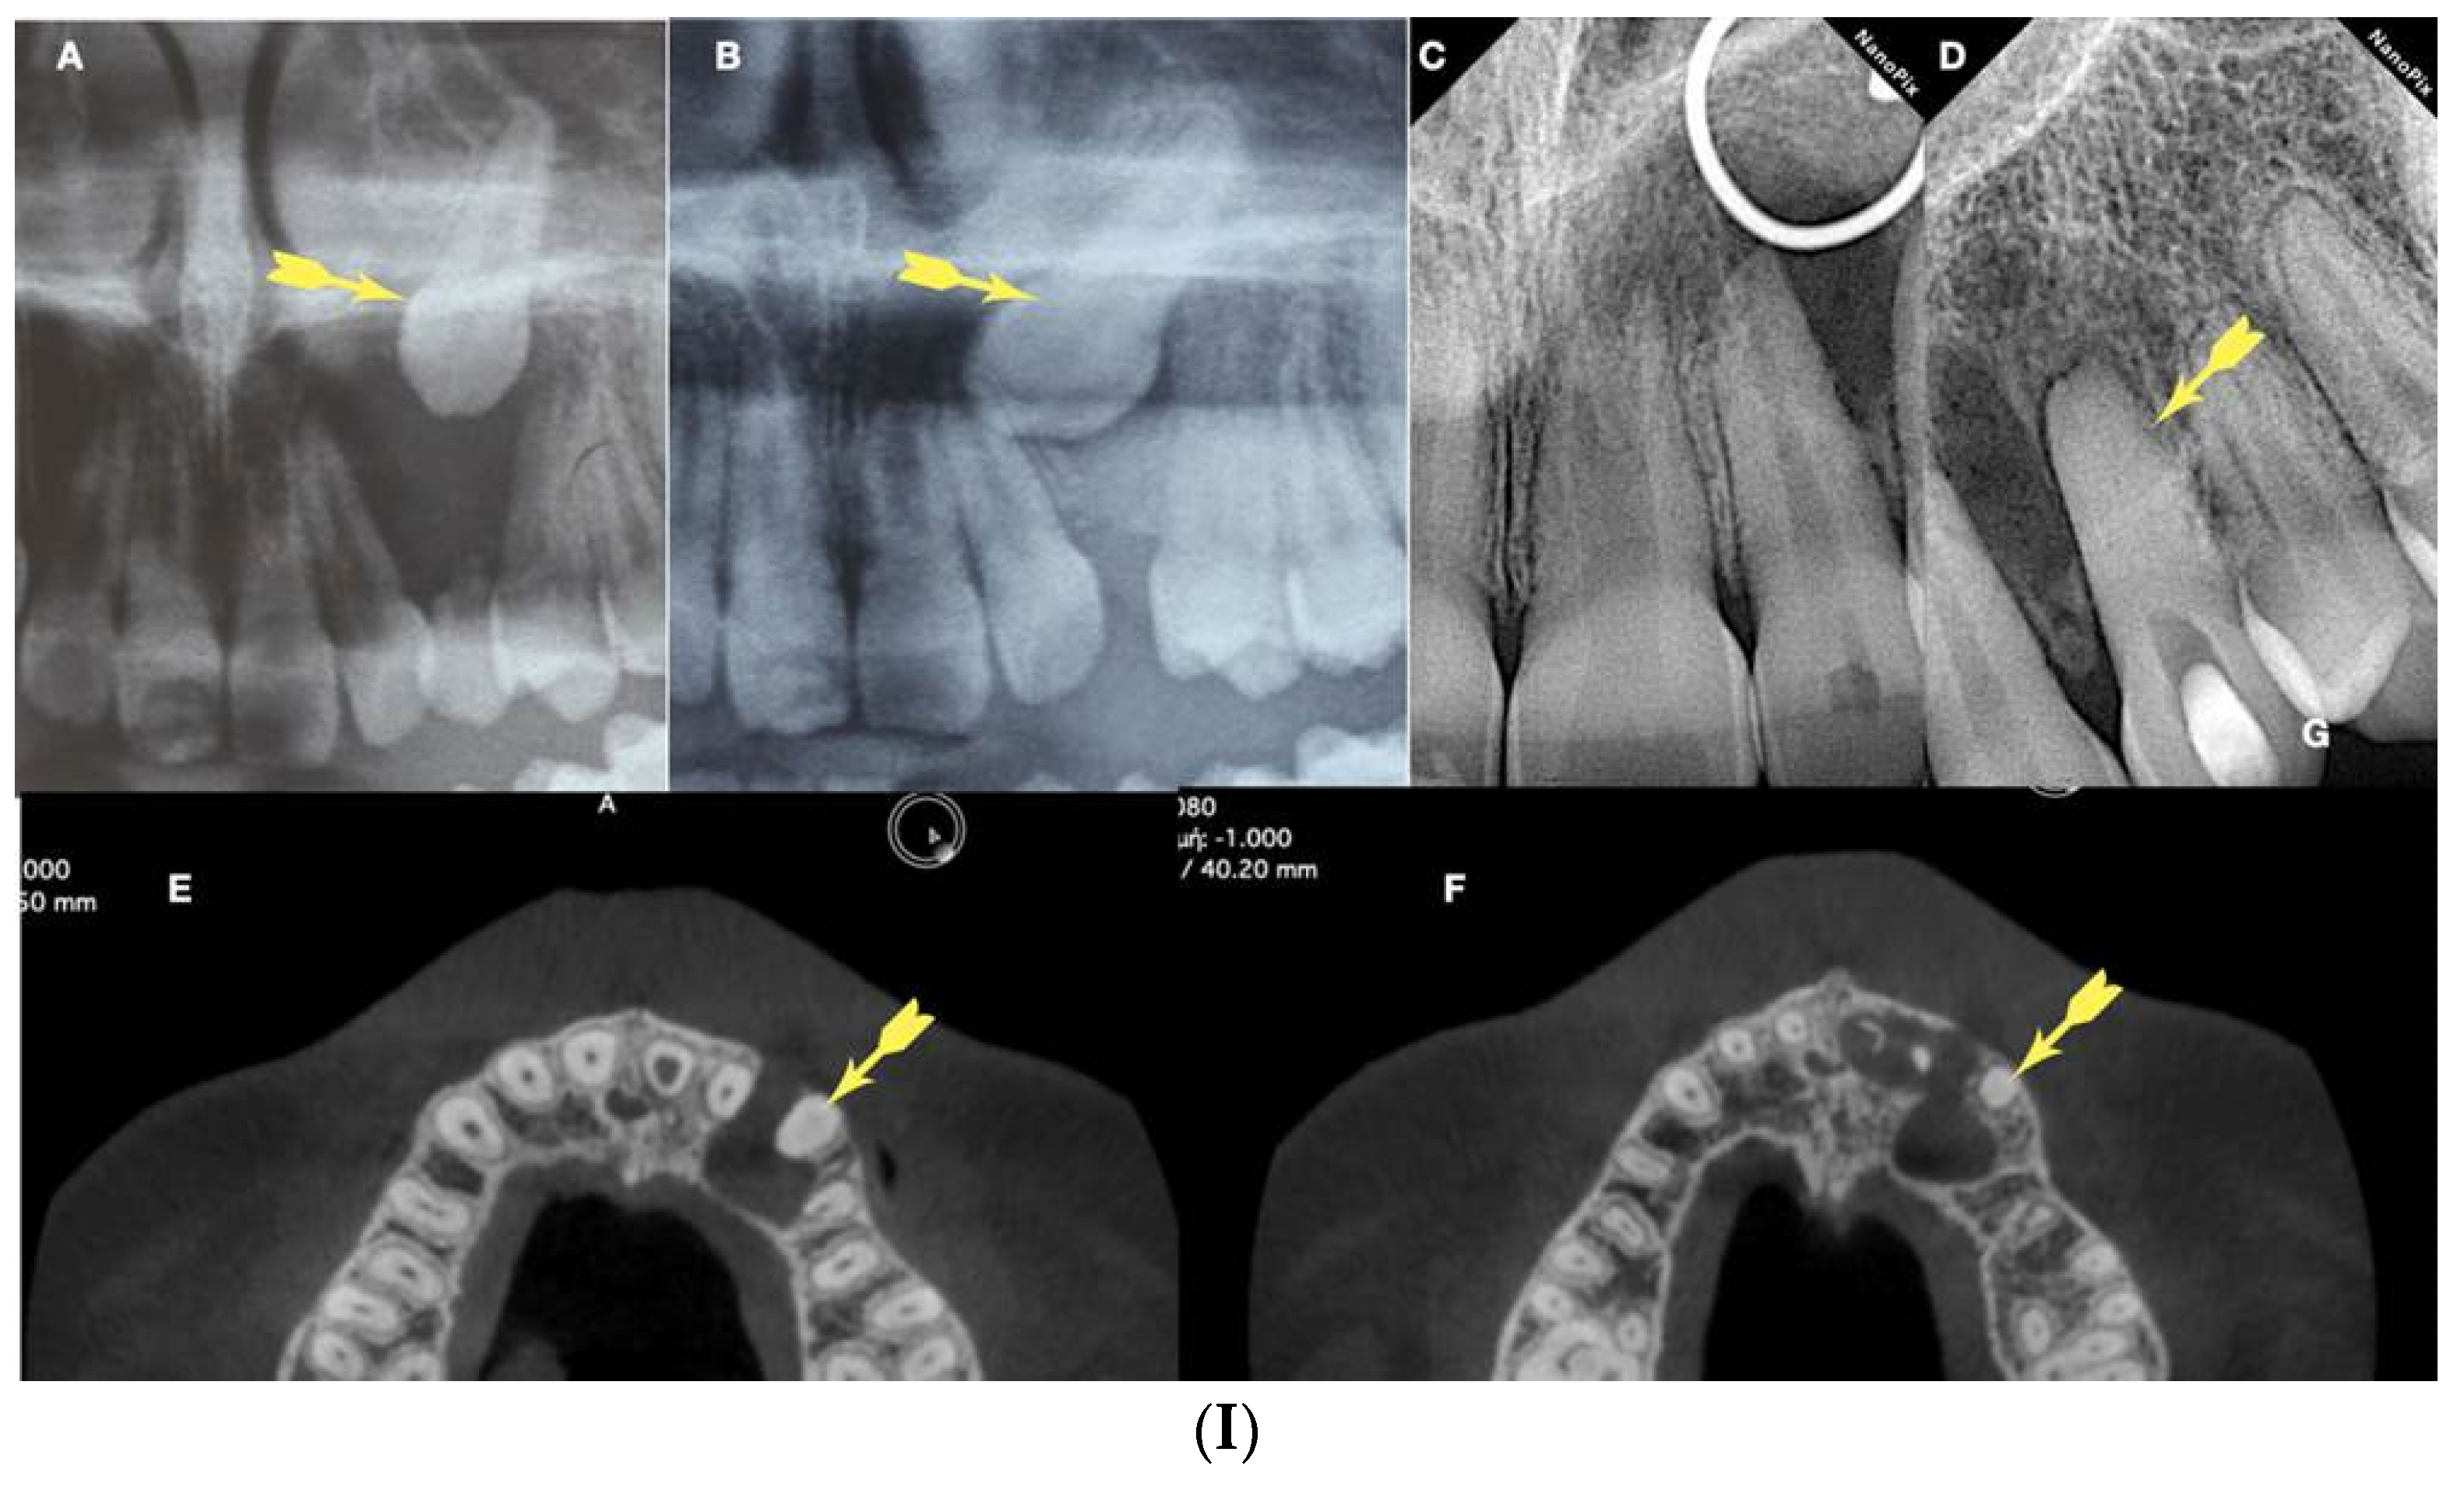

Figure 1.

a. Periapical radiograph of an abraded calcified mandibular incisor with no visible canal lumen, b. 3D Micro-ct reconstruction of the same calcified mandibular incisor that was extracted for prosthetic reasons. The micro-ct reveals a patent canal, c. Apical root canal anatomy of the calcified canal lumen sectioned revealing canal bifurcation and apical anastomosis. (Skyscan 1172 micro-CT scanning device, Bruker MicroCT, Belgium) (Images courtesy of dr. Alexey Volokitin).

Figure 2.

Axial micro-ct slices of the calcified mandibular incisor of

Figure 1 revealing the cross-sectional root canal dimensions along the root. The crown of the tooth is completely blocked, and the canal is visible starting at the level of the CEJ. The root canal dimensions are constricted in the coronal part of the root and become wider in the middle third of the root and splitting in the apical third into two canals. In calcified cases root canal dimensions usually present an inverted taper. (Skyscan 1172 micro-CT scanning device, Bruker MicroCT, Belgium). (Images courtesy of dr. Alexey Volokitin).